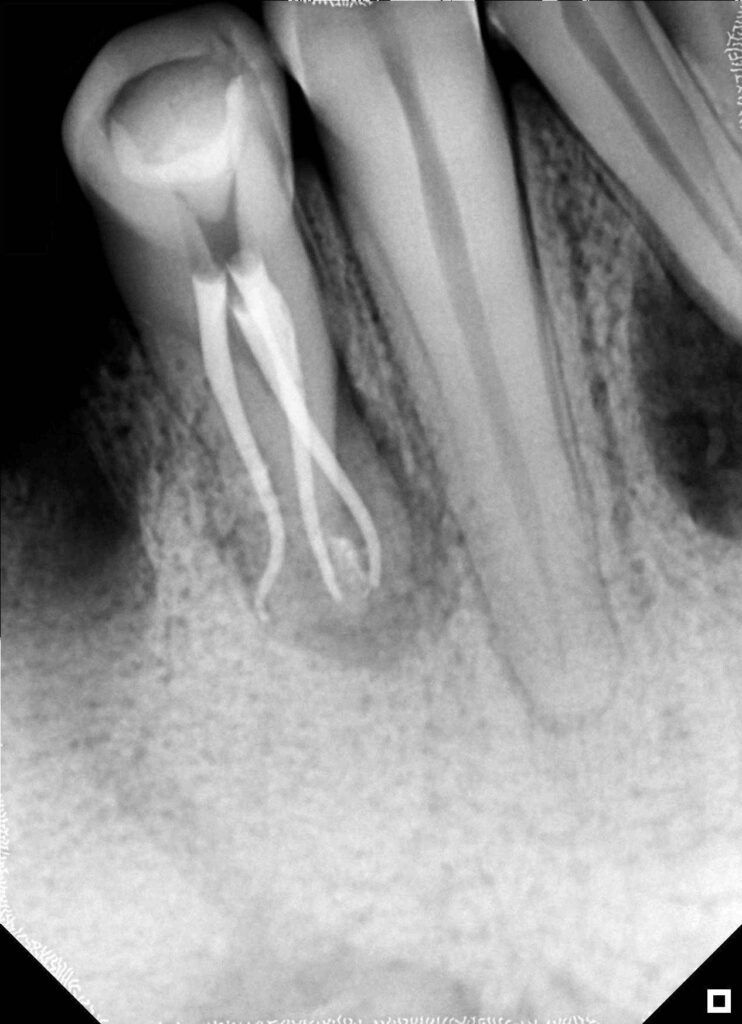

Evaluación radiográfica preoperatoria

La radiografía inicial revela una imagen sugerente de una división abrupta del conducto

principal antes del tercio medio. Se observa ensanchamiento del espacio del ligamento

periodontal e imagen radiolúcida apical, una anatomía radicular compleja que sugiere la

presencia de múltiples sistemas de conductos.